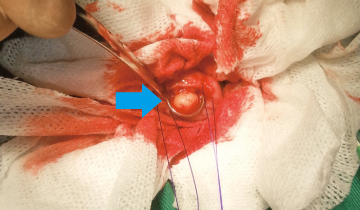

手術では膀胱を切開し、無事結石を全て摘出しました。

術後のレントゲン検査と超音波検査で結石が取り切れているのを確認。術後経過は良好で血尿も治まり退院しました。